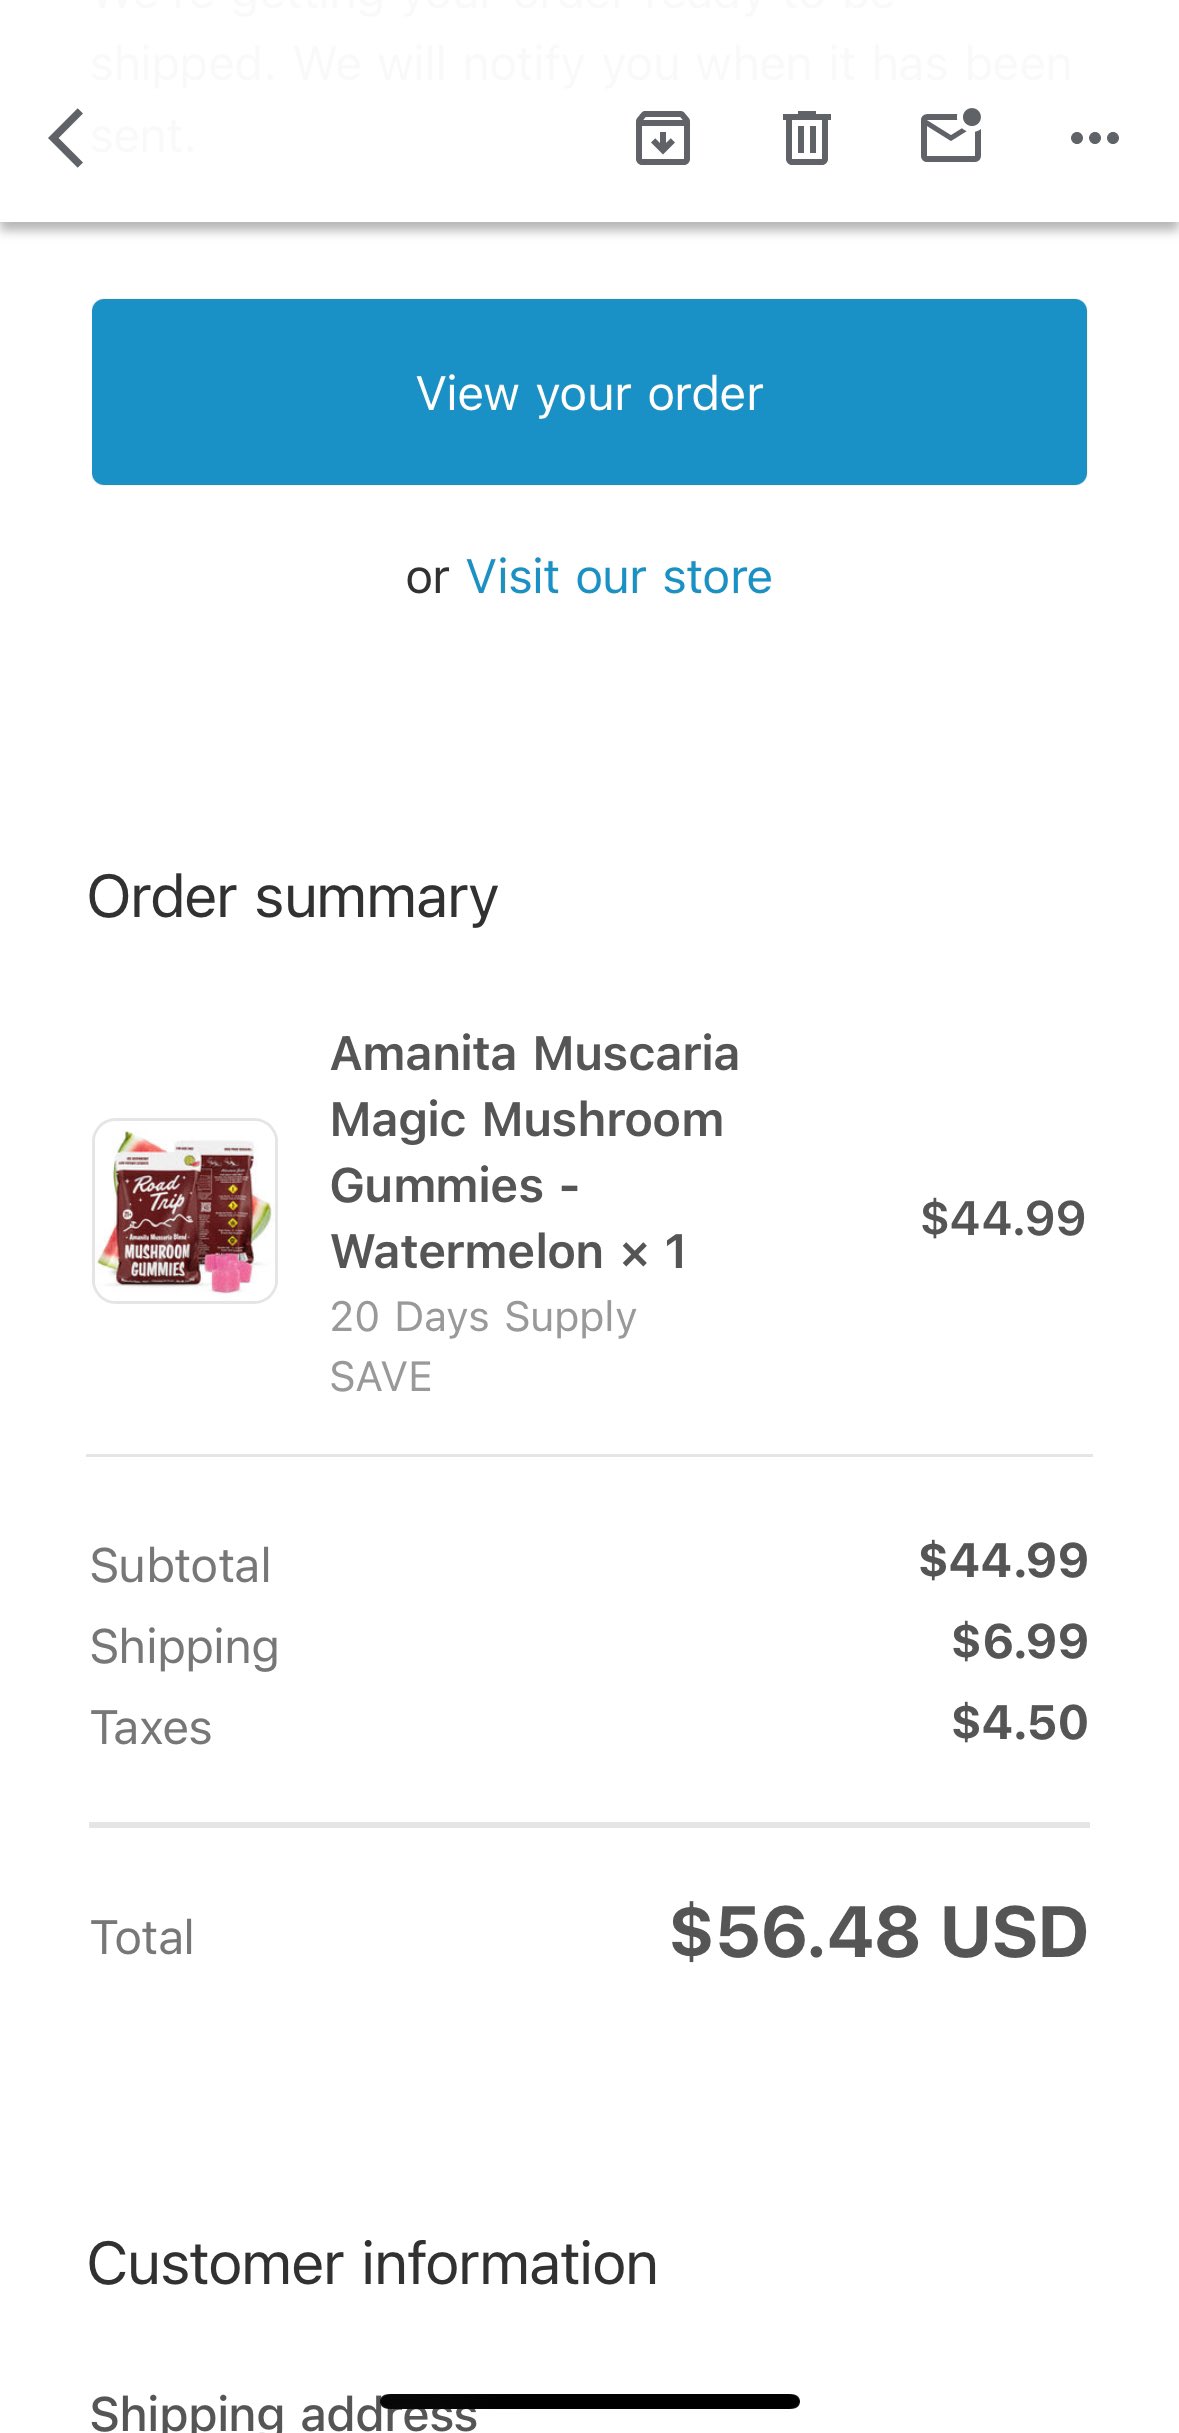

真的会推荐发作的时候或难治性抑郁做氯胺酮🥺关于价格,不算私立医院或住院的情况,一般一次是800...其实以前药费也有吃到过很高

不会像mect那样副作用很可怕,我的感觉是几乎没有负面影响

顺着这个思路用的auv对我效果也很好。那么漫长的寻找和尝试总算有了相对稳定的解法..太好了

炽烈已极 @AnIncandescence菜单(不是)

这本书挺好的,抗抑郁新疗法基本都提了,我大多都试过x

写了传统疗法,氯胺酮,经颅磁,电休克,运动睡眠营养,auv致幻剂mdma https://t.co/xTfmtUfIIk[图片媒体不可用]

Anoko @fawpv25@AnIncandescence 一次八百比我想象的便宜!而且有用的话是非常划算的!(多年前一个月吃药能花1k多…(((

炽烈已极 @AnIncandescence@fawpv25 有用的话真的是非常好的...试图拯救自己于疾病是非常合理的行为。每次觉得花了太多钱的时候只能试图如此说服自己TwT左右脑互搏

🥛💤 @Kumamushi2021@AnIncandescence 好想尝试…🥺真的不想再做MECT了对记忆的损伤好大

炽烈已极 @AnIncandescence@Kumamushi2021 我不是双相所以从来没有考虑过关于躁狂的问题…宝宝可能还是要和医生讨论一下比较好哦。但是我记得这个在排除风险之后连精分都可以做的(对于阴性症状很大帮助),所以适应症应该还比较广...

炽烈已极 @AnIncandescence@Idontselldrug 比较保险的是不伴有精神病症状的单相抑郁,双相我没试过所以不确定,条件是重症或多种药物疗效不佳,可能要做一些心电ct抽血之类的检查。主要还是看医院有没有开设这个治疗

炽烈已极 @AnIncandescence@Idontselldrug *是或。我去的地方口头是宣称就没问题了,不过本来他也无从查证呀,你吃过多少种药之类的